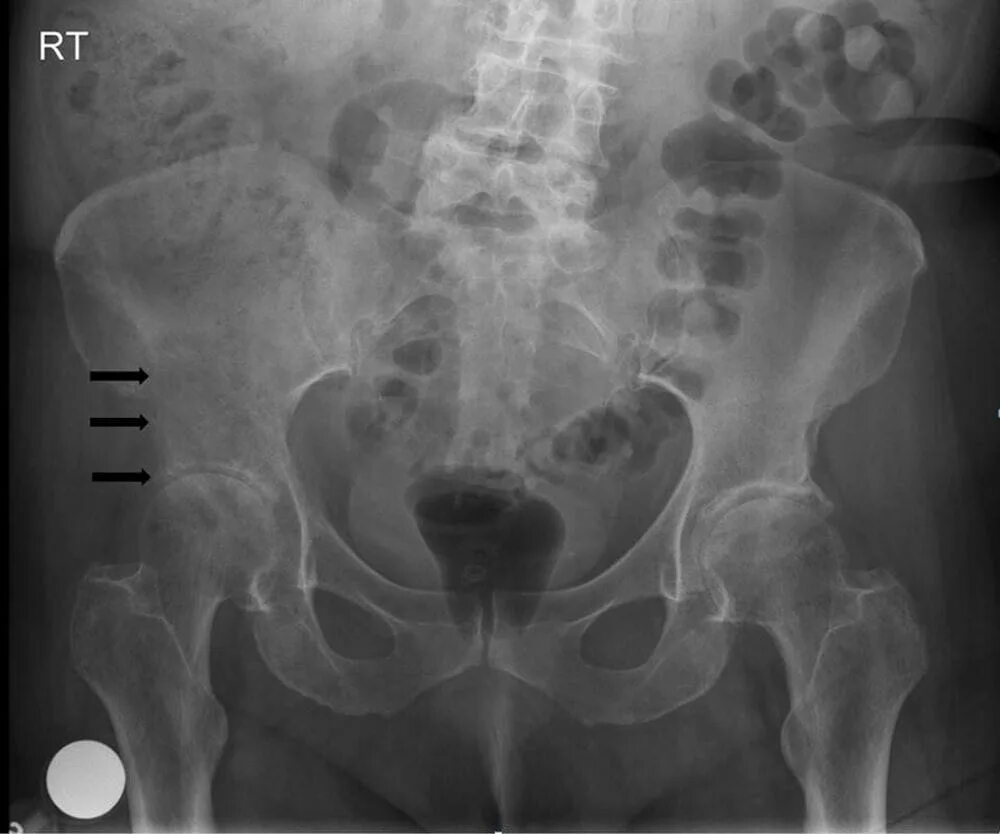

Метастазы в тазу